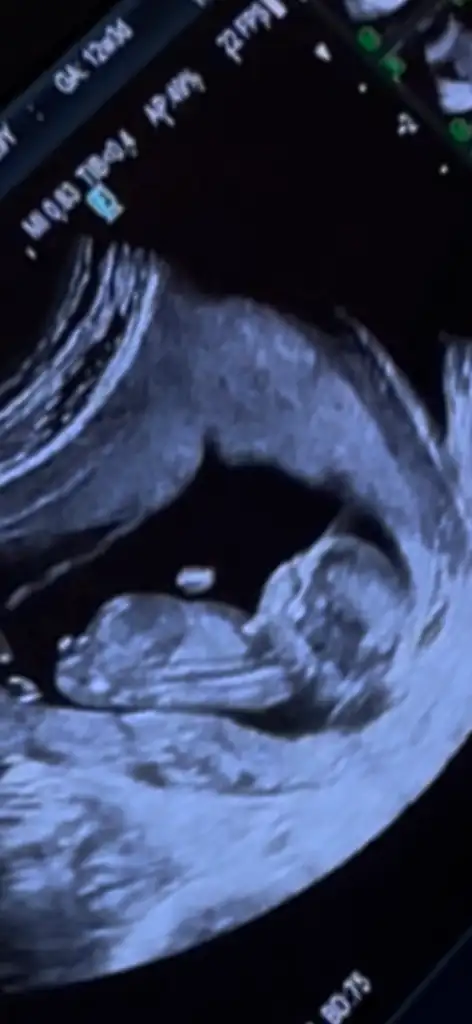

İlk resimde erkeğe benziyor ama kalça kemiği de olabilir dedi, 13 haftalık tam, bacağını kapatıyor, arkadan da boş görünüyor, pipi olsa arkadan görünür müNub şekline göre yorum yaptım öğrenebildiniz mi

Kız sanırım bacak arası boş görünüyor ben size benim resmi ekleyeyim videodan çektim 14 haftalıktı öğrendiğim deİlk resimde erkeğe benziyor ama kalça kemiği de olabilir dedi, 13 haftalık tam, bacağını kapatıyor, arkadan da boş görünüyor, pipi olsa arkadan görünür mü

Sizinki kız miKız sanırım bacak arası boş görünüyor ben size benim resmi ekleyeyim videodan çektim 14 haftalıktı öğrendiğim de

ErkekSizinki kız mi